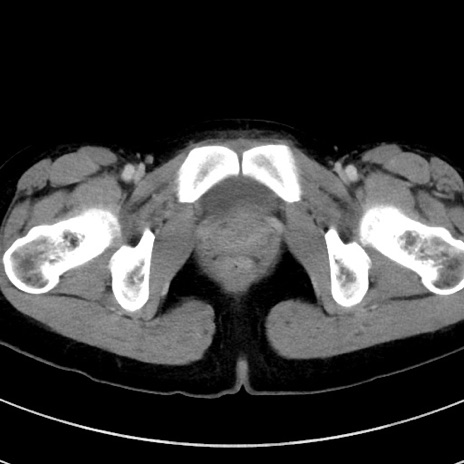

冠状断像

【症例】20歳代女性

【主訴】嘔吐、下腹部痛

【現病歴】昨日夕食後に嘔吐し下腹部痛が出現。本日になっても嘔吐持続し改善しないため来院。

【身体所見】意識清明、BT 37.2℃、BP 108/67mmHg、腹部:平坦、やや硬、下腹部正中から右にかけて圧痛あり、反跳痛軽度あり、tapping pain(+)。

【データ】WBC 13600、CRP 14.94